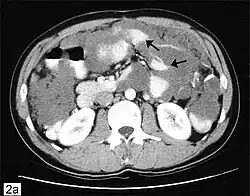

CT scanning is preferred to assess the extent of the tumor in the abdominopelvic cavity, though magnetic resonance imaging can also be used.[28] CT scanning can also be useful for finding omental caking or differentiating fluid from solid tumor in the abdomen, especially in low malignant potential tumors. However, it may not detect smaller tumors. Sometimes, a chest x-ray is used to detect metastases in the chest or pleural effusion. Another test for metastatic disease, though it is infrequently used, is a barium enema, which can show if the rectosigmoid colon is involved in the disease. Positron emission tomography, bone scans, and paracentesis are of limited use; in fact, paracentesis can cause metastases to form at the needle insertion site and may not provide useful results.[29] However, paracentesis can be used in cases where there is no pelvic mass and ascites is still present.[29] A physician suspecting ovarian cancer may also perform mammography or an endometrial biopsy (in the case of abnormal bleeding) to assess the possibility of breast malignancies and endometrial malignancy, respectively. Vaginal ultrasonography is often the first-line imaging study performed when an adnexal mass is found. Several characteristics of an adnexal mass indicate ovarian malignancy; they usually are solid, irregular, multilocular, and/or large; and they typically have papillary features, central vessels, and/or irregular internal septations.[31] However, SCST has no definitive characteristics on radiographic study.[32]

In advanced cancers, where complete removal is not an option, as much tumor as possible is removed in a procedure called debulking surgery. This surgery is not always successful, and is less likely to be successful in women with extensive metastases in the peritoneum, stage- IV disease, cancer in the transverse fissure of the liver, mesentery, or diaphragm, and large areas of ascites. Debulking surgery has usually only been done once[28] but a recent study has shown a longer overall survival in recurrent ovarian cancer when surgery combined with chemotherapy was performed compared to treatment with chemotherapy alone.[100] Computed tomography (abdominal CT) is often used to assess if primary debulking surgery is possible, but low certainty evidence also suggests fluorodeoxyglucose‐18 (FDG) PET/CT and MRI may be useful as an addition for assessing macroscopic incomplete debulking.[101] More complete debulking is associated with better outcomes: women with no macroscopic evidence of disease after debulking have a median survival of 39 months, as opposed to 17 months with less complete surgery.[26] By removing metastases, many cells that are resistant to chemotherapy are removed, and any clumps of cells that have died are also removed. This allows chemotherapy to better reach the remaining cancer cells, which are more likely to be fast-growing and therefore chemosensitive.[29]